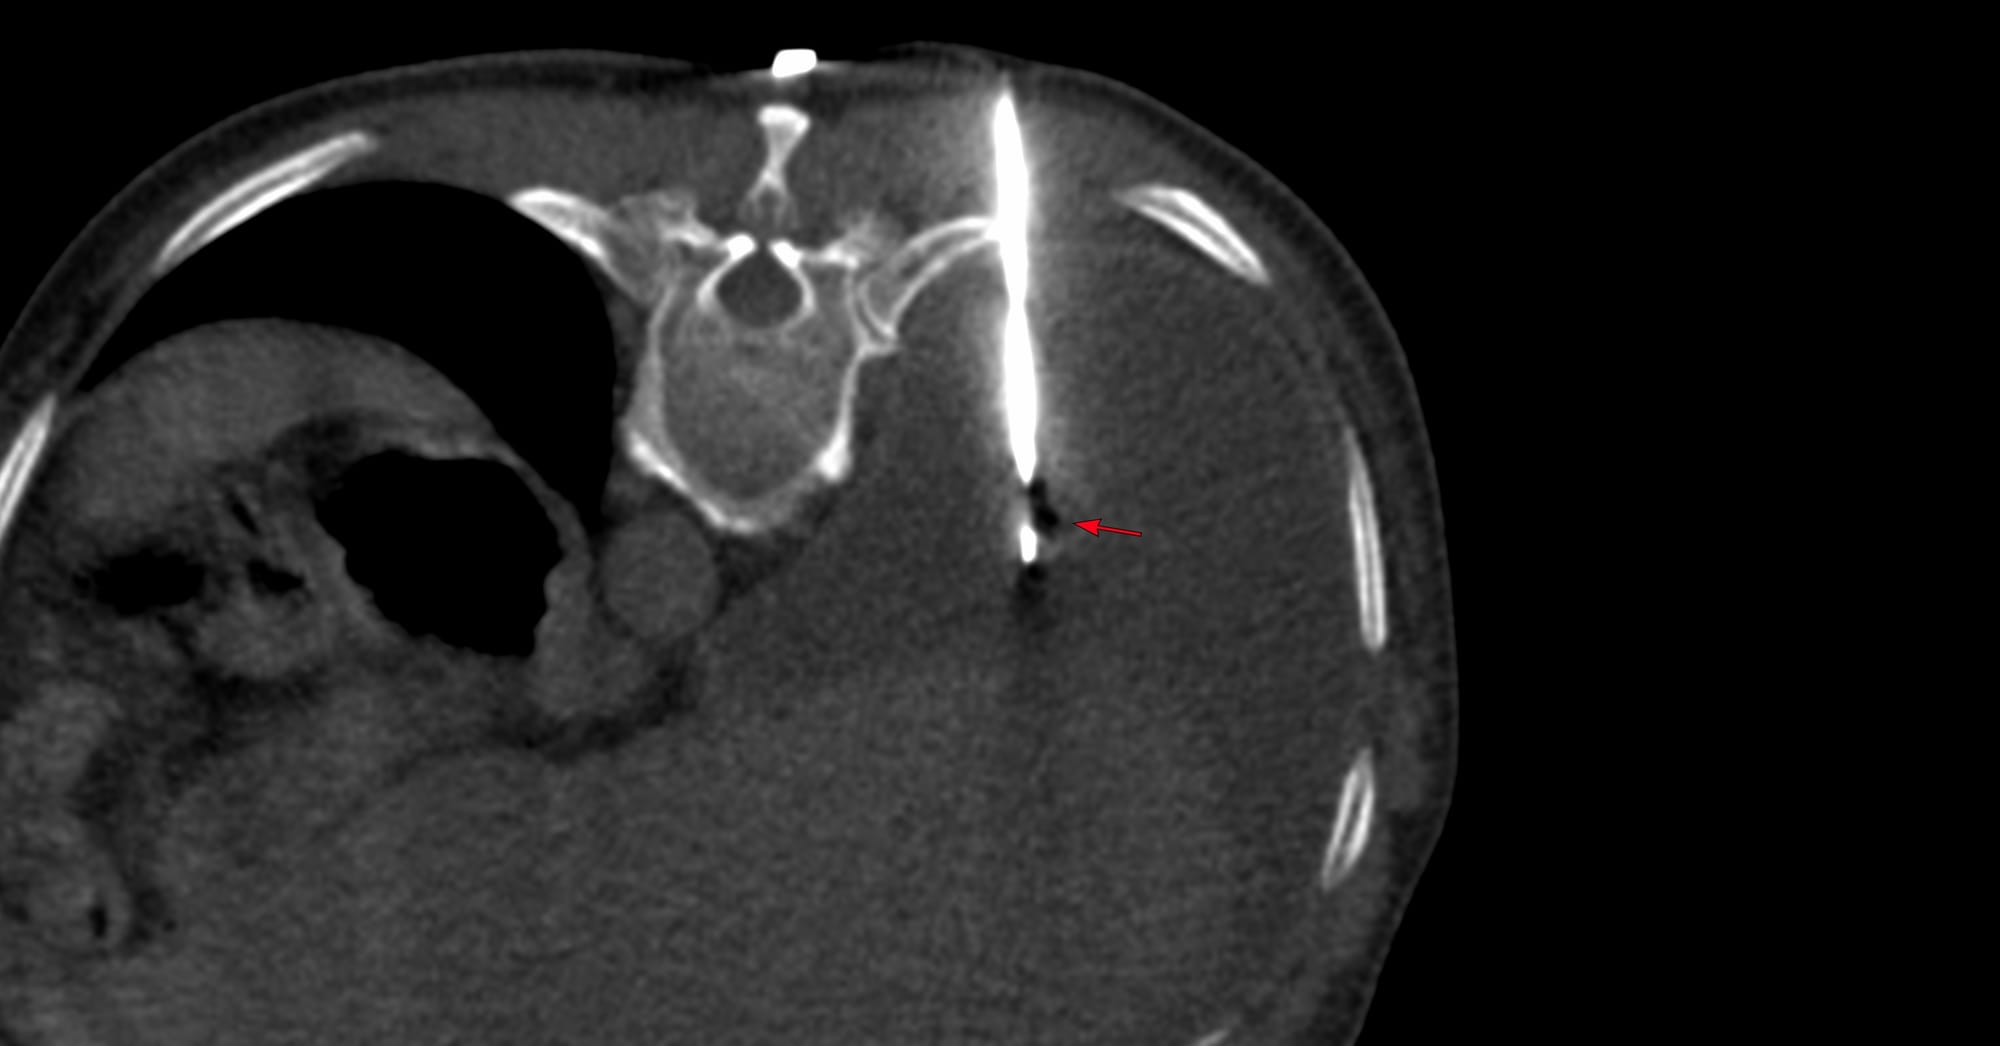

Case of the Day 100 - 2025 09 10 - T2 Dark Thoracic Spinal Vertebral Lesion - Transpedicular Biopsy

Bhavin Jankharia - 14 September 2025

Case of the Day - 098 - 2025 09 08 - Confirming Tuberculosis of the Lower Cervical Spine

Bhavin Jankharia - 09 September 2025